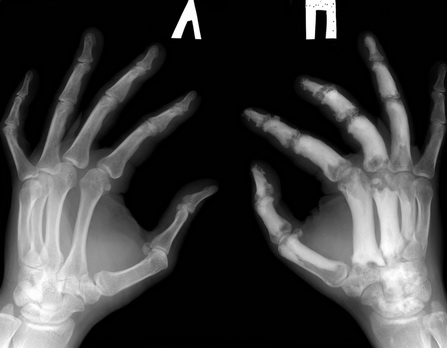

Уважаемые коллеги помогите. Для какого заболевания характерна такая R-картина

Обратился пациент на прием. Травмы не было. Болеет(со слов) в течении 10лет, никогда и никуда

не обращался, лечился сам чем мог. Анамнез не отягощенный. Последние 2мес. отмечает

значительное ухудшение, болит правая кисть, ни с чем не связывает. Более подробно напишу

клинику и лабораторные показатели при явке пациента после дообследования